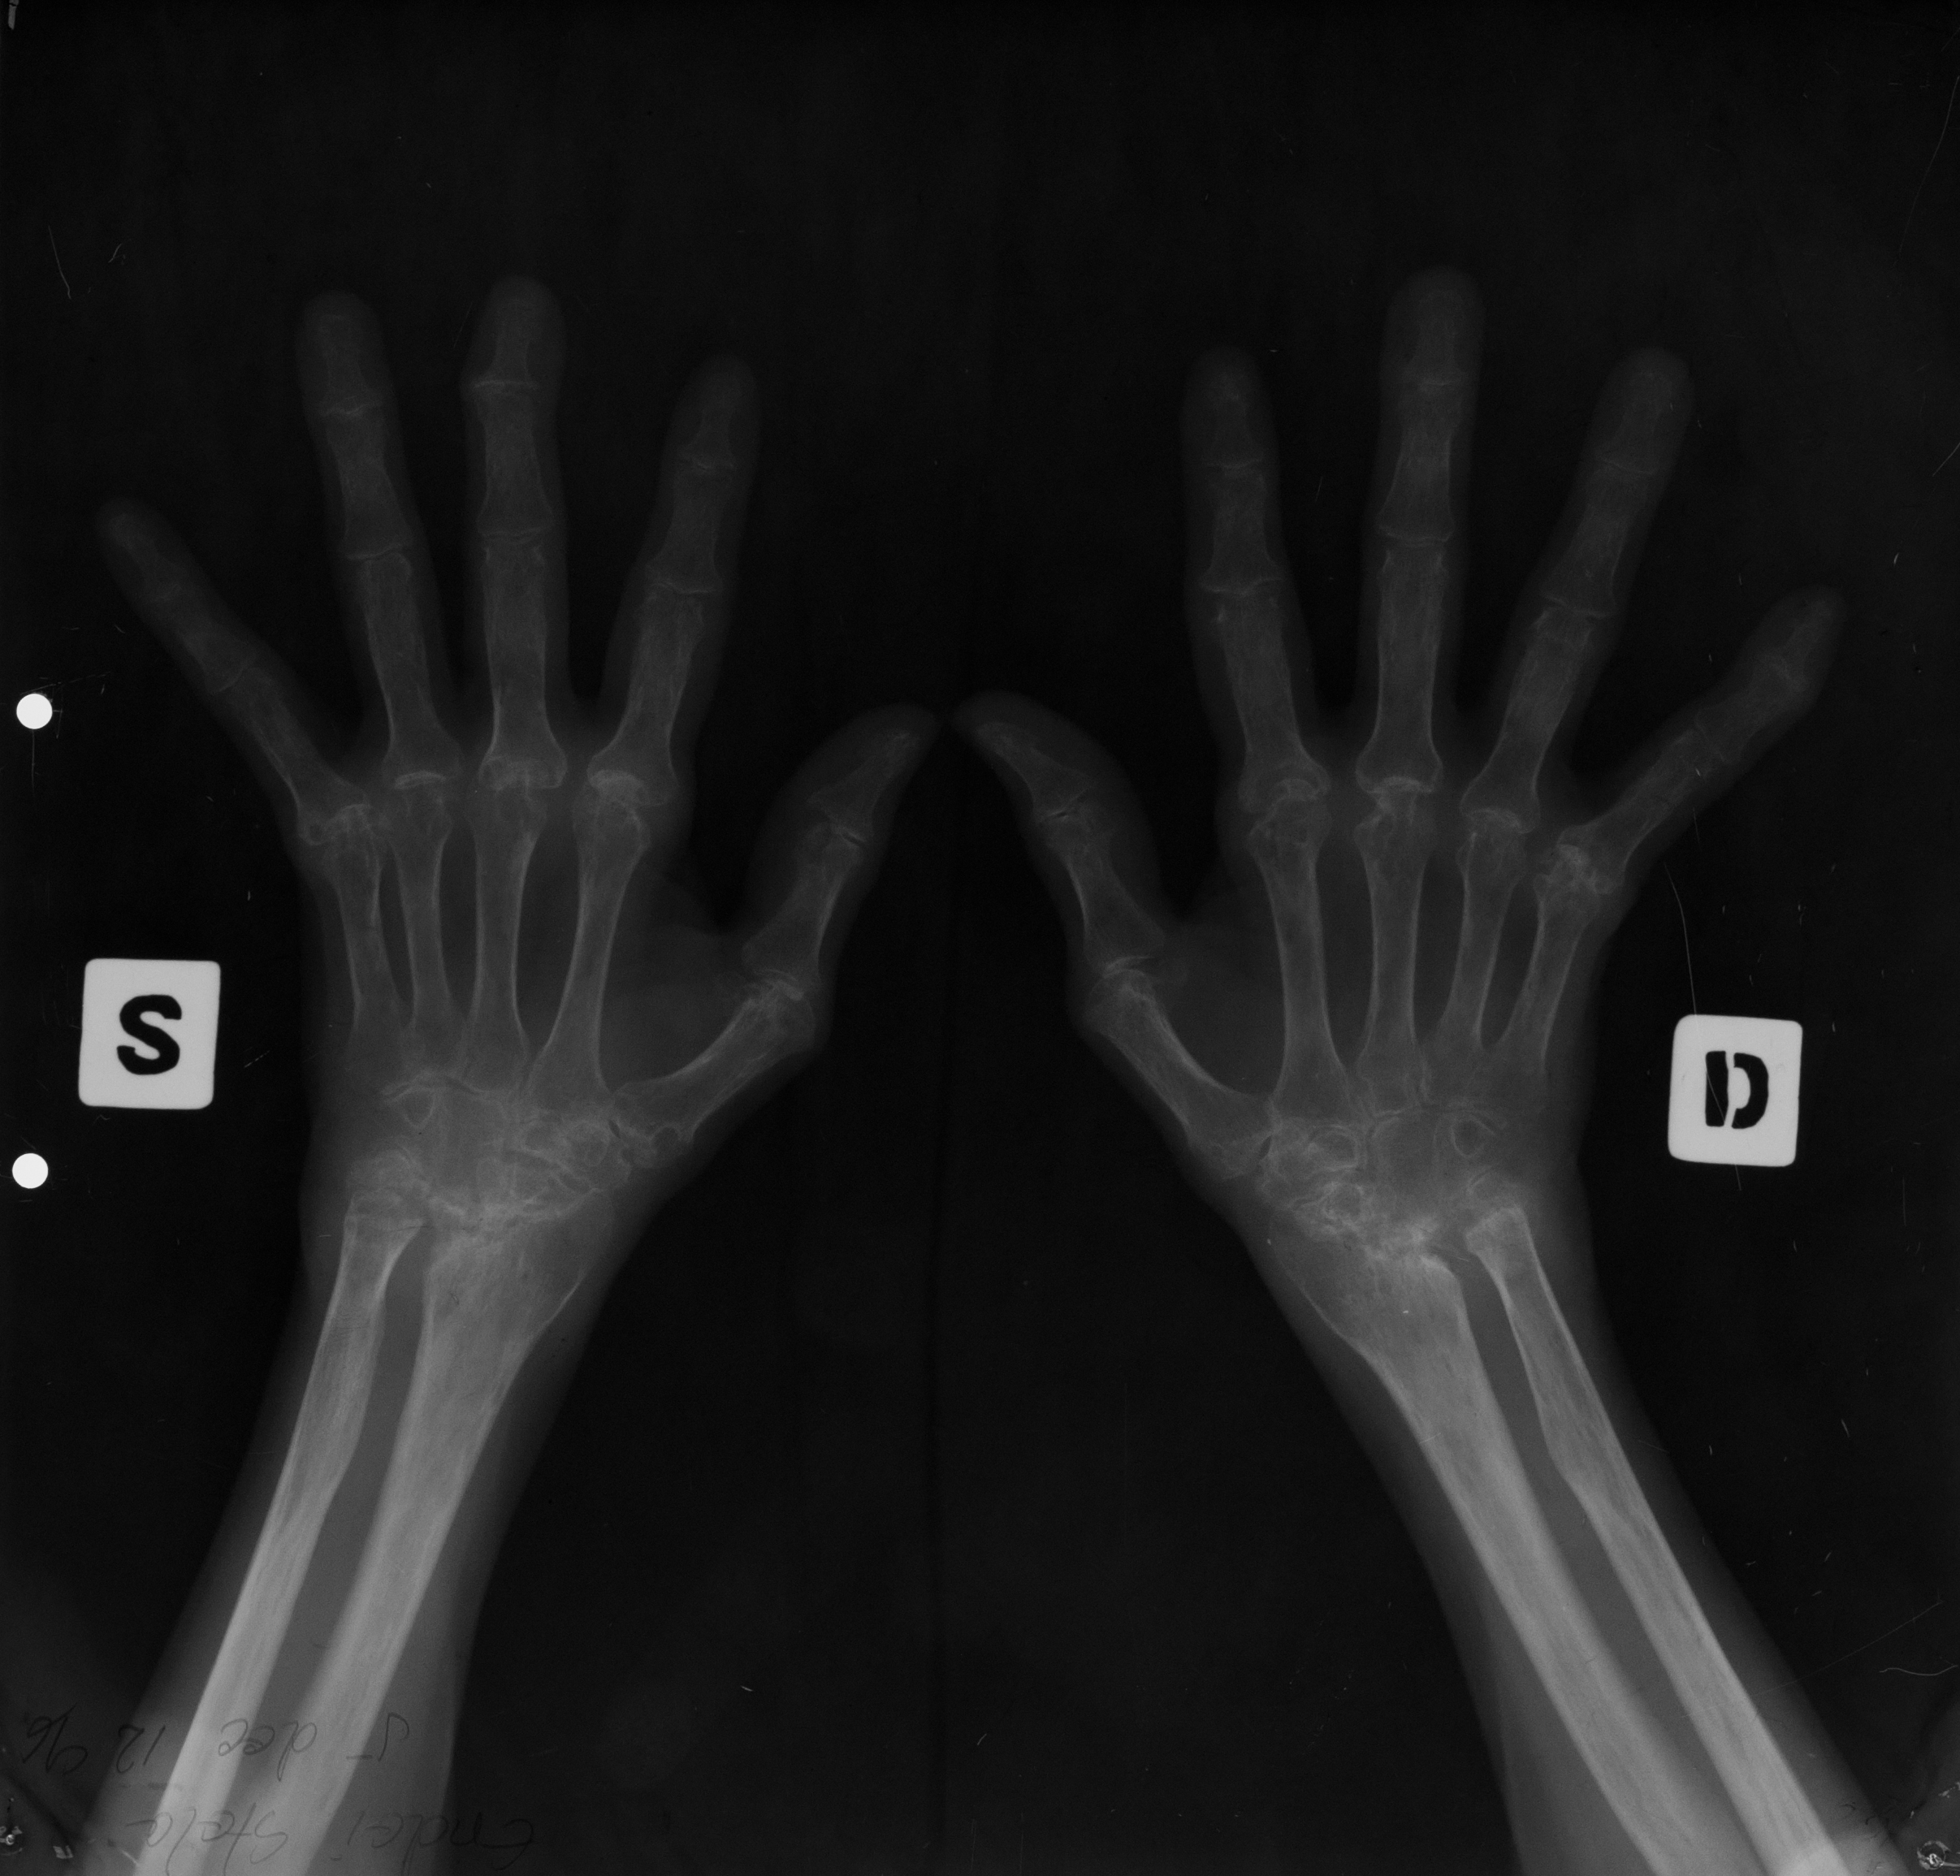

Osteoporoza in bandă, care e stadiul incipient (stadiul I) de poliartrită reumatoidă

Radiografie comparativa de maini, in care se vede o transparenta crescuta a extremitatilor metacarpienilor (adica a capetelor metacarpienilor, respectiv a bazelor falangelor)

Stadiul II spre III de poliartrita reumatoida

Radiografie comparativa de maini, cu osteoporoza accentuata, cu spatii disparute la nivelul oaselor carpiene si lize semnificative la nivelul spatiilor articulare interfalagiene proximale (deci bazele falangelor, respectiv capetele falangelor proximale), lize marginale cu disparitie de spatii articulare – stadiul 2 spre 3 de poliartrita reumatoida

MODIFICĂRI DE STADIUL 3 DE POLIARTRITĂ REUMATOIDĂ

Osteoporoză accentuată,absenta spațiilor articulare și distrucția severă ale oaselor carpiene,lize,osteolize și subluxații ale falangelor una pe cealaltă cu derivație pe cubitus(derivație cubitală)